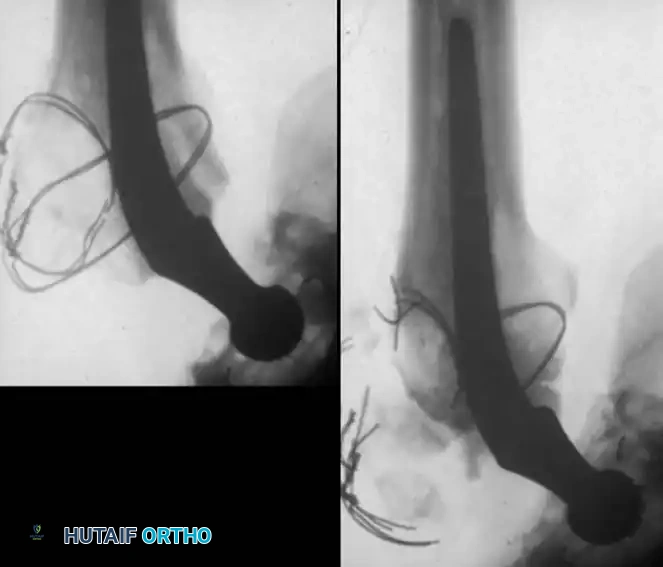

Associated Surgical & Radiographic Imaging